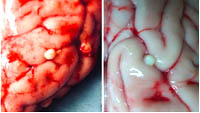

Hình 6. Một số thương tổn do ấu trùng sán dây lợn trên hệ thần kinh